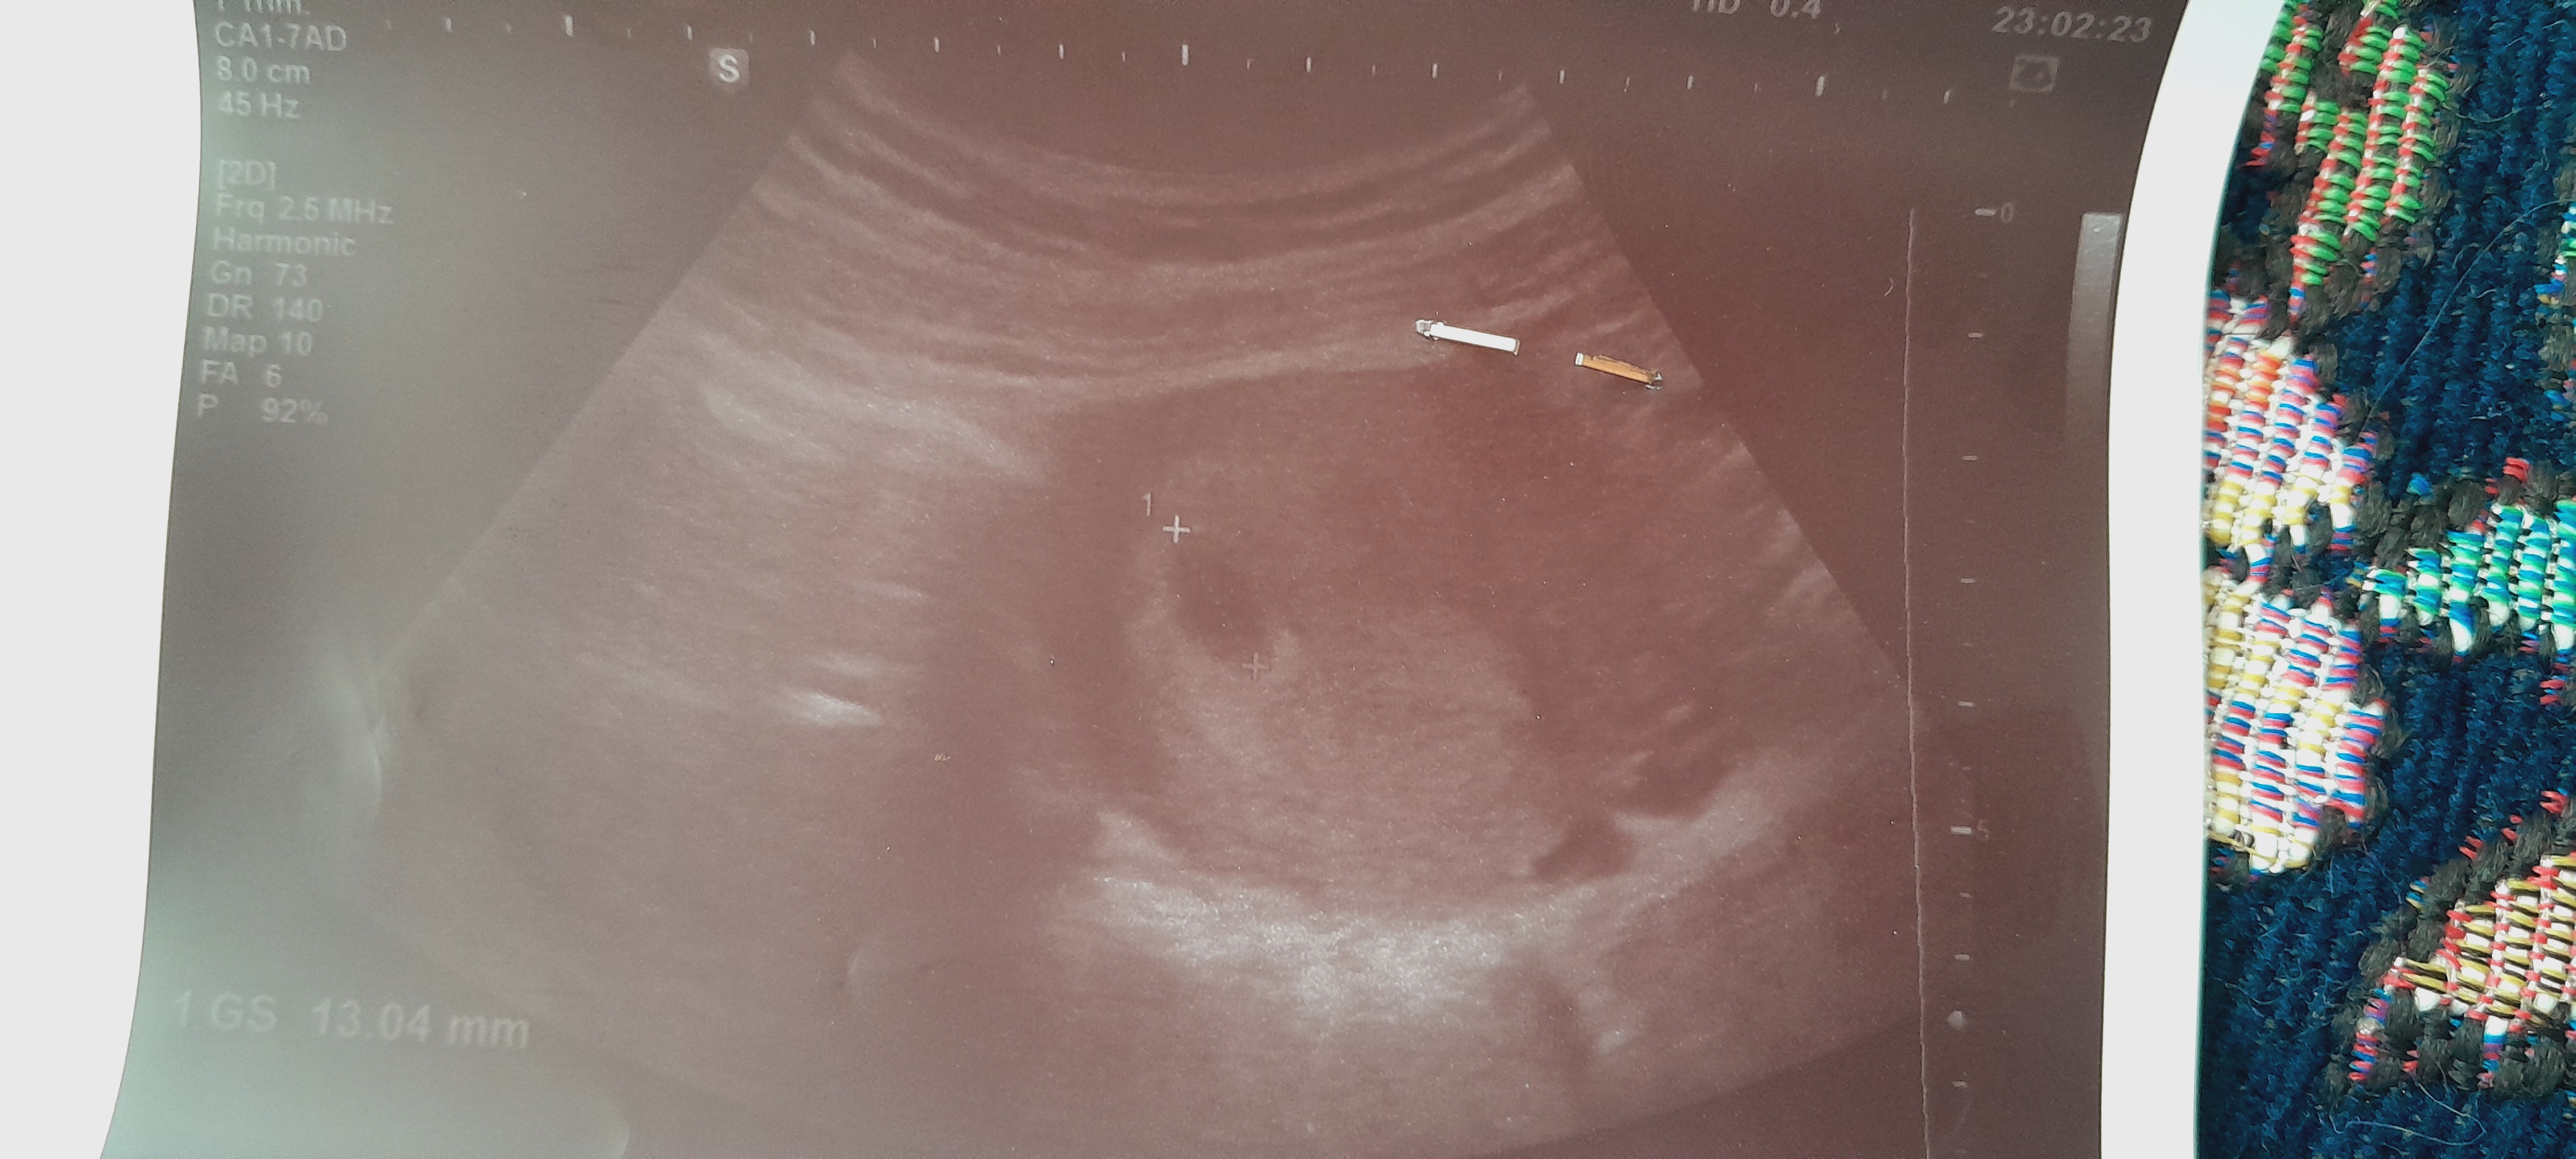

سلام دوستان ببخشید بعضی وقتا درد پایین شکم دارم درست پایین شکم فقط بغلش کمردرد بعضی وقتا هم دارم اینا طبیعی هست خیلی نگرانم میکنه بخاطر همین دردا رفتن سونو گفتم خوبه ساک و کیسه زرده تشکیل شده فقط چون تو ۵ هفته گی اومدی جنین و نمیشه دید هفته دیگه سونو دارم تو ۷ هفته این دردا عادیه خیلی میترسونه منو فقط هم سینه درد و نفخ دارم یکی هم از شیرینی بدم میاد تازگیا دوغ دوست دارم😂

عزیزم عکس سونوت می‌فرستی ببینم چپش کجاست راست کجاست

من رفتم سونو عکسم داده

تو عکسه سمت راسته

سمت راست عکس میشه سمت چپ من؟